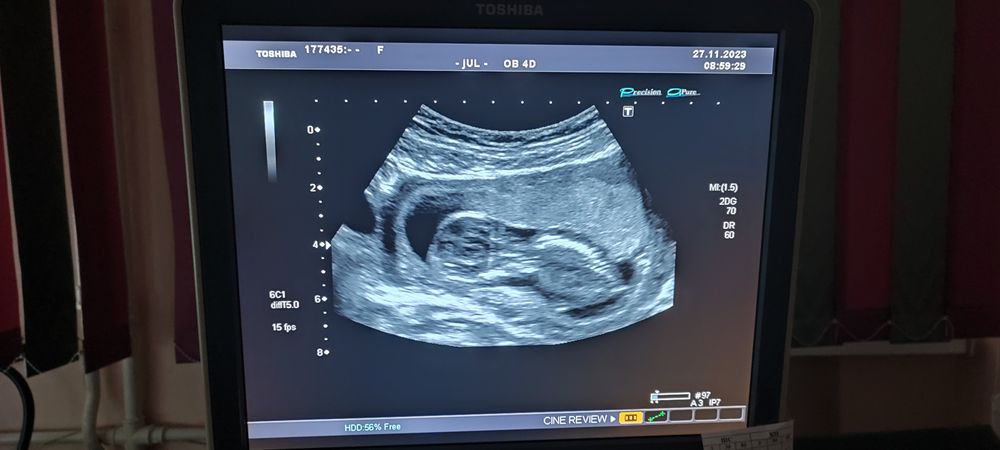

Какая прелесть! Я поздравляю вас от всей души, пока читала текст, ощущения были, будто я свой результат анализа читаю, настолько проникалась вашей ситуацией))) правда мне наоборот нужен женский пол 🤭☺️ ура-ура!! Расти, крепчай, мальчишечка!! 💜💫🚀 Ваше УЗИ из сегодняшнего поста настолько мне напомнило головы моих парней, что я почти не сомневалась что там у вас сыночек ☺️

Виктория , я тоже когда детей сравнила, увидела, что малышок будто побольше, и прям голова больше. Но старалась не очаровываться, потому что могу себе придумывать. Теперь понимаю, что да, малышок покрупнее))) Благодарю за пожелания! 🤗🤗🤗

Узи мальчик На 1 скрининге сказали, что, вероятно, мальчик